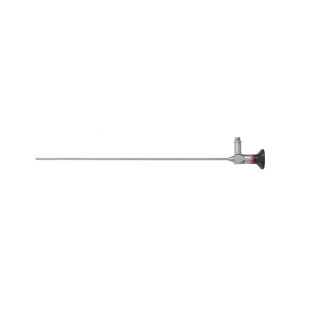

방광 경성 내시경

방광 경성 내시경 -